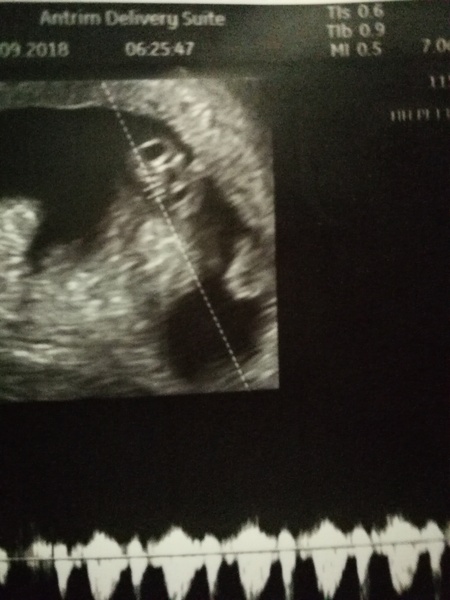

Just went to the ultrasound that I had booked before bfp to test for pcos. Told them about the spotting and asked if they could check everything was okay. They showed me the baby, 5 weeks 5 days with a little heart beat :) now feel a little guilty dh wasn't there to see it but very relieved 😌

Then, this evening was our early scan at Mothercare! So wonderful. Measured 8+4 and I'm 8+6 on last period date so that was all within normal range. And saw the little heart beating. So comforting to see that something is actually in there. Looking forward to the 12week scan now.

I woke up in so much pain, I thought it was an ectopic pregnancy. A&E doc agreed with me even though HCG levels were normal and pushed for a scan. Well, guess what! There's a healthy wee baby in there :). Oh, and I have a kidney infection, but I can deal with that.